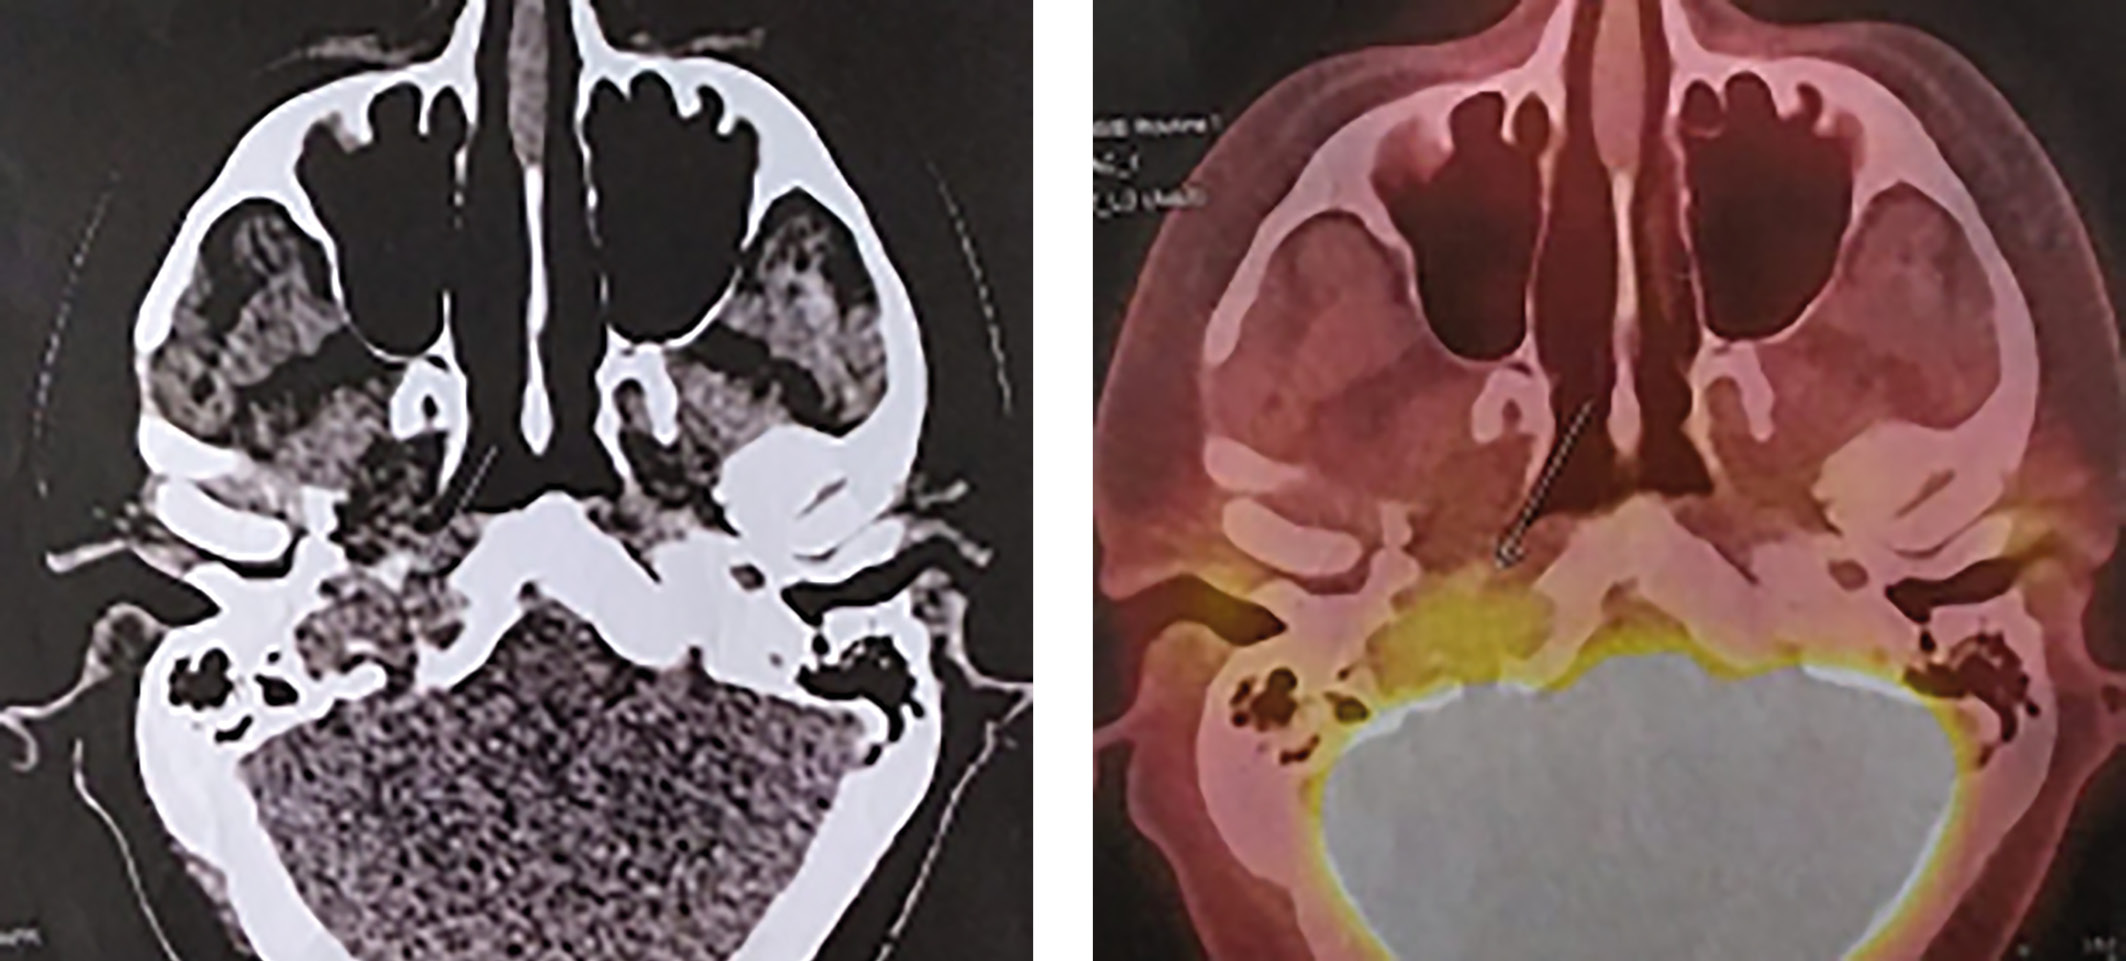

Пациенту была проведена ПЭТ-КТ с 18F-ФДГ — получены данные о наличии активной опухолевой ткани в костях основания черепа справа. Других очагов патологического накопления радиофармпрепарата не выявлено (рис. 2).

Рисунок 2. На серии ПЭТ/КТ выявляются очаги патологического накопления 18F-ФДГ: в большом крыле клиновидной кости справа с макс SUV 4,85, по КТ — мягкотканное образование, деструирующее клиновидную кость и прилегающие участки ската и пирамиды правой височной кости с образованием внекостного компонента, распространяющегося интракраниально и дистально по ходу внутренней сонной артерии до уровня С1, размерами около 2,8х1,5 см (указано стрелкой).